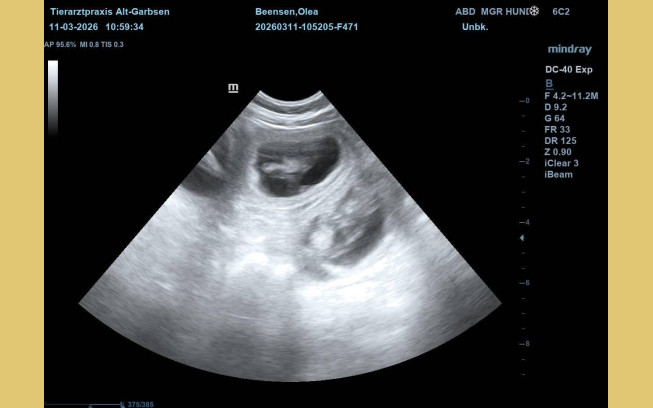

Update vom 11.03.2026:

Heute war ein ganz besonderer Tag. Olea war zum Ultraschall. Schon seit einigen Tagen hatten ihre Besitzer das Gefühl, dass sich etwas verändert hat. Sie war ruhiger und anhänglicher geworden - und ihr Bäuchlein schien sich leicht zu runden.

Beim Ultraschall war es dann eindeutig. Kleine, deutlich erkennbare Welpen. Auf dem Bildschirm waren mehrere winzige Herzschläge zu sehen. Freude, Aufregung und Ehrfurcht - alles zusammen stellte sich bei den Besitzern ein. Olea lag ganz entspannt - als wüsste sie, dass in dem Moment etwas ganz Wundervolles passiert. Jetzt beginnt die spannende Zeit der Vorbereitung. In den nächsten Wochen wird alles für die Ankunft der kleinen "vom Jademeer´chen" vorbereitet. Nicht mehr lange.....